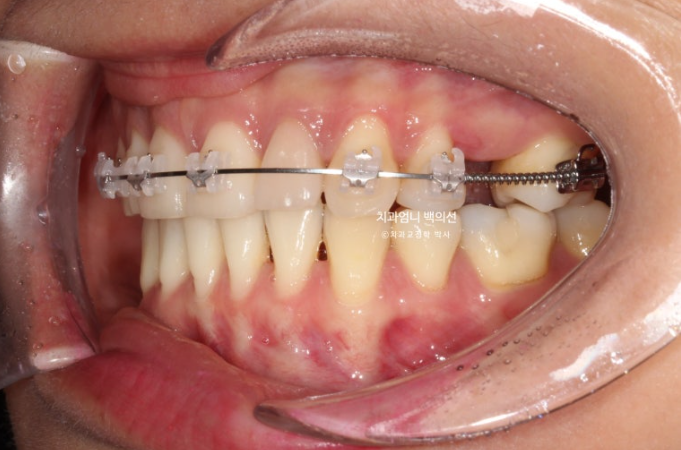

24.04

치료시작 6개월차 모습입니다.

위에만 장치를 붙여서 치료를 진행하고 있습니다.

큰어금니 공간을 회복하면서 말입니다.